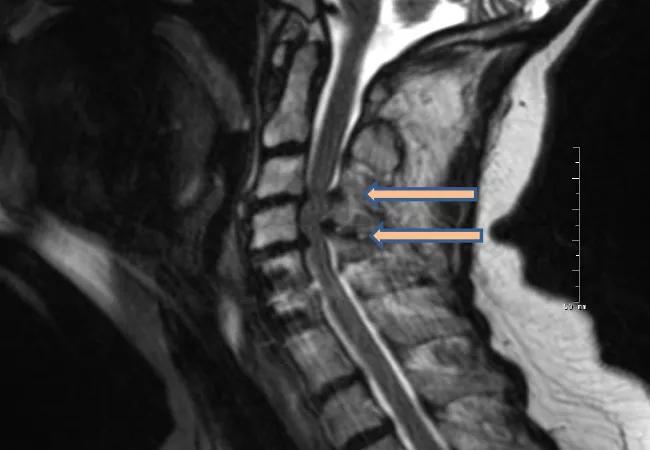

Patients with Parkinson’s disease (PD) may exhibit symptoms similar to those observed in cervical spondylotic myelopathy (CSM), including ataxia, weakness, and bowel or bladder dysfunction. These similarities present diagnostic and therapeutic challenges when PD and CSM coexist. While CSM is typically treated with surgical decompression (Figure), PD requires pharmacologic therapies and is expected to derive little benefit from decompression. This poses a dilemma for both neurologists and spine surgeons treating patients with PD who may have evidence of cervical spondylosis and myelopathy.

Figure. (A) Preoperative sagittal T2 MRI of a patient with coexistent cervical spondylotic myelopathy and Parkinson disease. Note the severe cervical stenosis and cord compression at C3-4and C4-5 (arrows). (B) Postoperative X-ray after the patient underwent laminectomies at C3 through C5 and extension of her fusion to C3 via a dorsal approach.